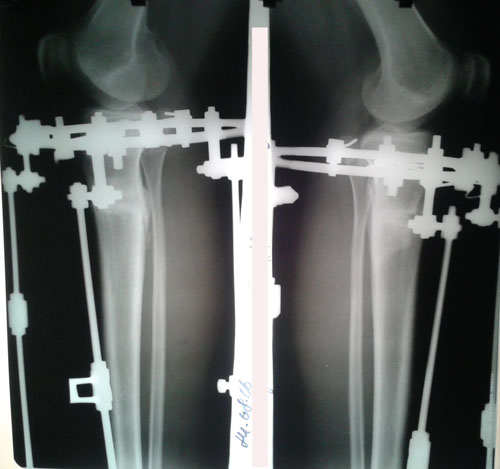

На фиксации.

image-09-07-16-01-27.jpg